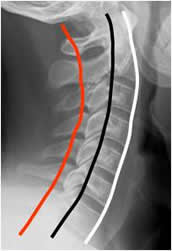

La alineación de la columna cervical en la proyección lateral, se determina trazando las líneas arcuatas. Son la vertebral anterior, vertebral posterior y la espinolaminar. (5). (Fig 3). Igualmente se deben tener en cuenta los espacios prevertebral y retrofaringeo, que se aumenta en casos de patología. El prevertebral se mide entre C1 y C4 y debe ser menor de 7 mm o el 30% del ancho del cuerpo vertebral. El retroesofágico entre C5 y C7 debe ser menor de 14 mm en los adultos y menor de 22 mm en los niños o igual al ancho del cuerpo vertebral. (5). (Fig 4A y B).

Fig 3. Líneas arcuatas.

Rx lateral. Línea vertebral anterior. (Blanca). Vertebral posterior (Negra) y espinolaminar (Roja).